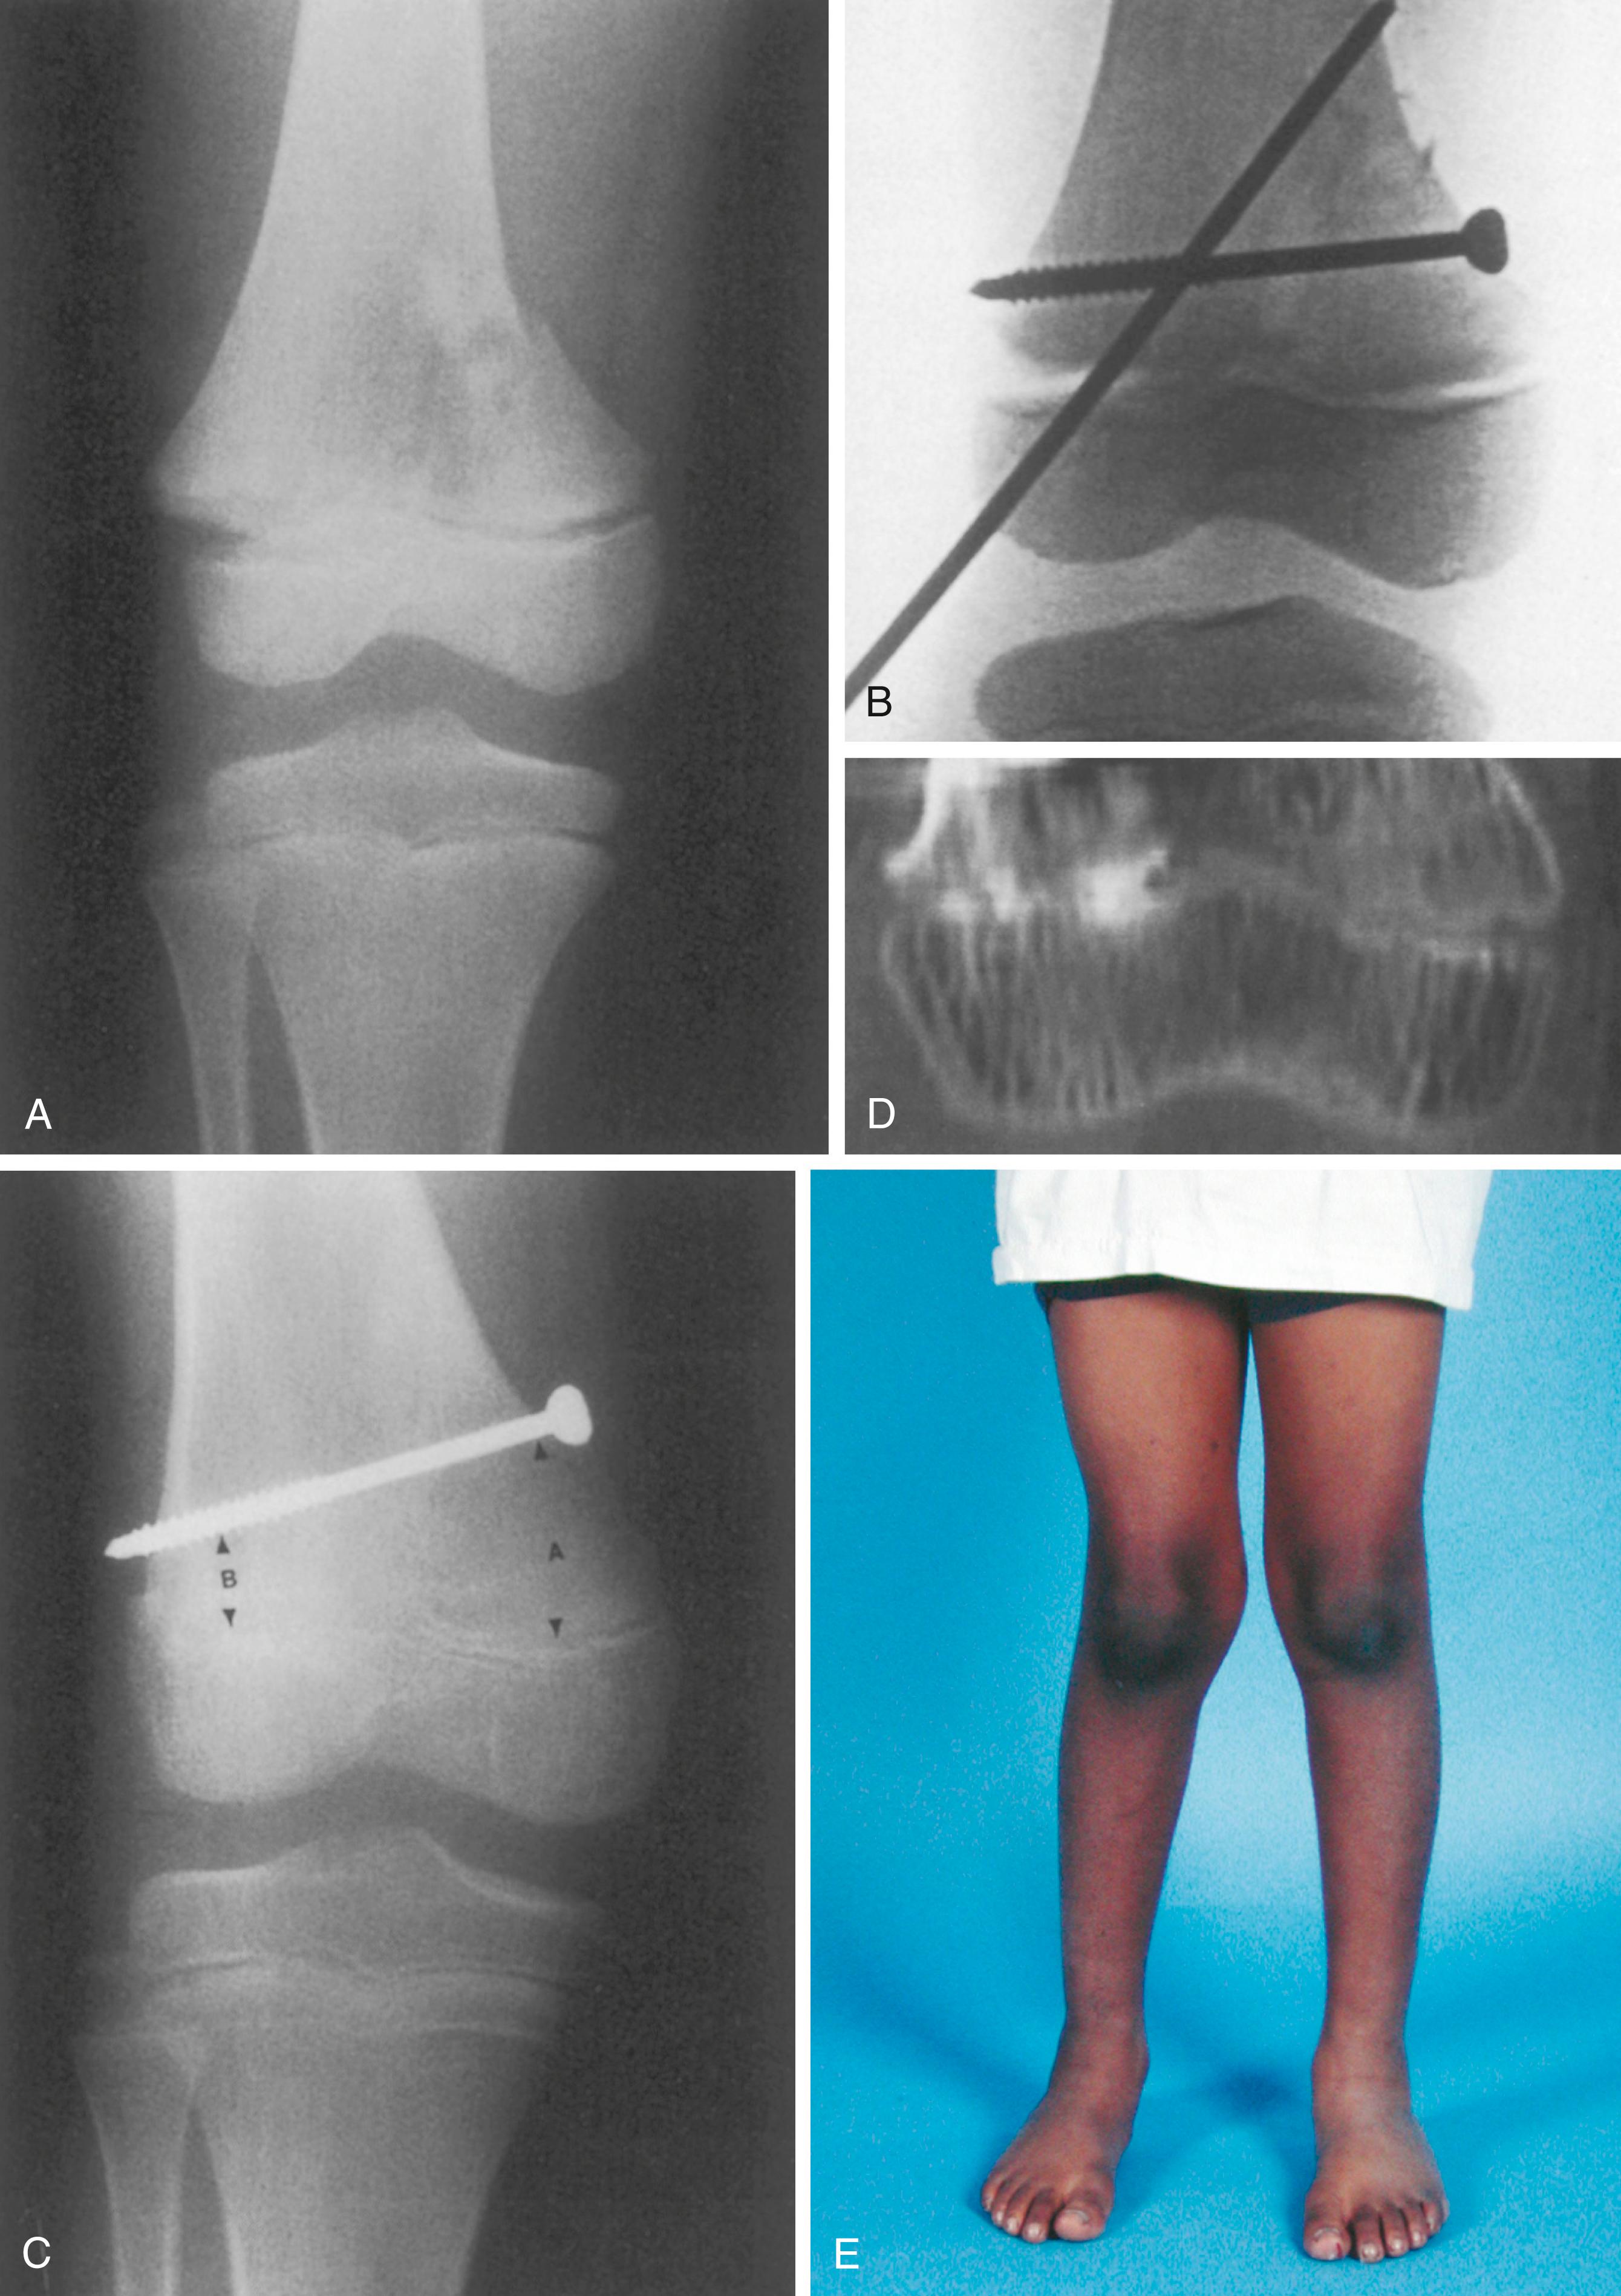

Fig. 27.15, Physeal arrest producing angular deformity. (A) Salter-Harris type II fracture of the distal femur. (B) Immediate postreduction film. (C) Anteroposterior radiograph 9 months after injury. The distance between the physis and the screw medially (A) is substantially greater than it was immediately after surgery. However, the distance laterally (B) is relatively unchanged. Note the radiodense appearance of the physis laterally. (D) Computed tomography scan demonstrating lateral bar formation. (E) The asymmetric growth has produced a valgus clinical appearance.